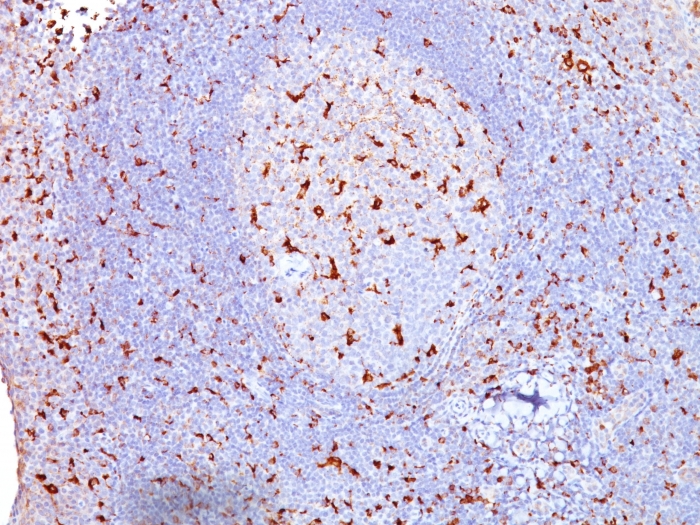

Product information "Anti-CD68 (Macrophage Marker), clone SPM130"

Formulation: Purified Ab WITHOUT BSA and Azide at 1.0mg/ml. Cellular Localization: Cell membrane, Endosome membrane, Lysosome membrane. Positive Control: lymph node or spleen., Tonsil. Chromosome Location: 17p13.1. Protein Function: Could play a role in phagocytic activities of tissue macrophages, both in intracellular lysosomal metabolism and extracellular cell-cell and cell-pathogen interactions. Binds to tissue- and organ-specific lectins or selectins, allowing homing of macrophage subsets to particular sites. Rapid recirculation of CD68 from endosomes and lysosomes to the plasma membrane may allow macrophages to crawl over selectin-bearing substrates or other cells [The Uniprot Consortium]

| Application: | FC, IF, IHC |